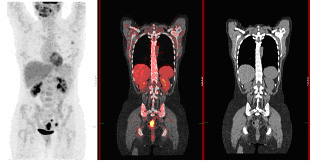

Clinical PET/CT

Establishing a clinical protocolClinical applicationsArtefacts and normal variantsClinical Imaging with 68Ga PET - Radiopharmaceuticals and Therapy